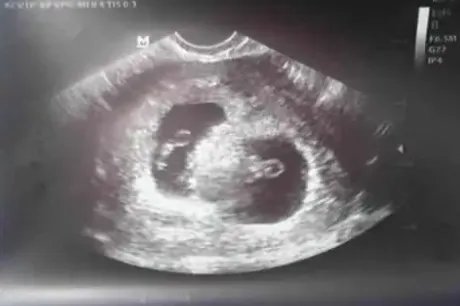

双胎胎心位置示意图

的有关信息介绍如下:双胎胎心,两胎儿心跳不全相同。在不同部位听两胎心音时,每分钟差10余次,或者两胎心音间有无音区相隔。

双胎胎心的定位可在发现胎儿胎位后进行。胎心率部位通常随胎位不同而异,但是胎儿发育时胎心率部位可分为3个时期,通常胎儿心率方向和胎儿体位同侧。孕妇首先要找胎儿所在,其次要找胎儿心率,会更容易找出来,找双胎心率和找单胎心率基本一致。

通常双胎心率之差约为10次。双胎心率出现差异也很正常,不必过于着急。双卵双胎时,可表现为2个受精卵着床时间不同,其中1个着床稍迟,因而造成孕囊发育的不同。即同时受精但到子宫的时间不同。注意少动、经常听诊胎心、监测血压、谨防妊娠期糖尿病、妊娠高血压综合症。